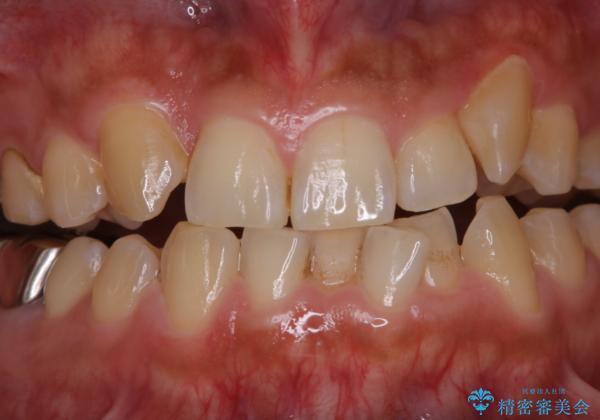

前歯メインにステインの付着が見られ、コース内容を相談した結果PMTC(保険外治療)の30分コースを行いました。

PMTCは30分コースと60分コースがあります。お口の中の状態を診断し適切なコースの説明・ご案内を行っています。

当日担当者と相談し、ご希望のコースを選択していただいております。